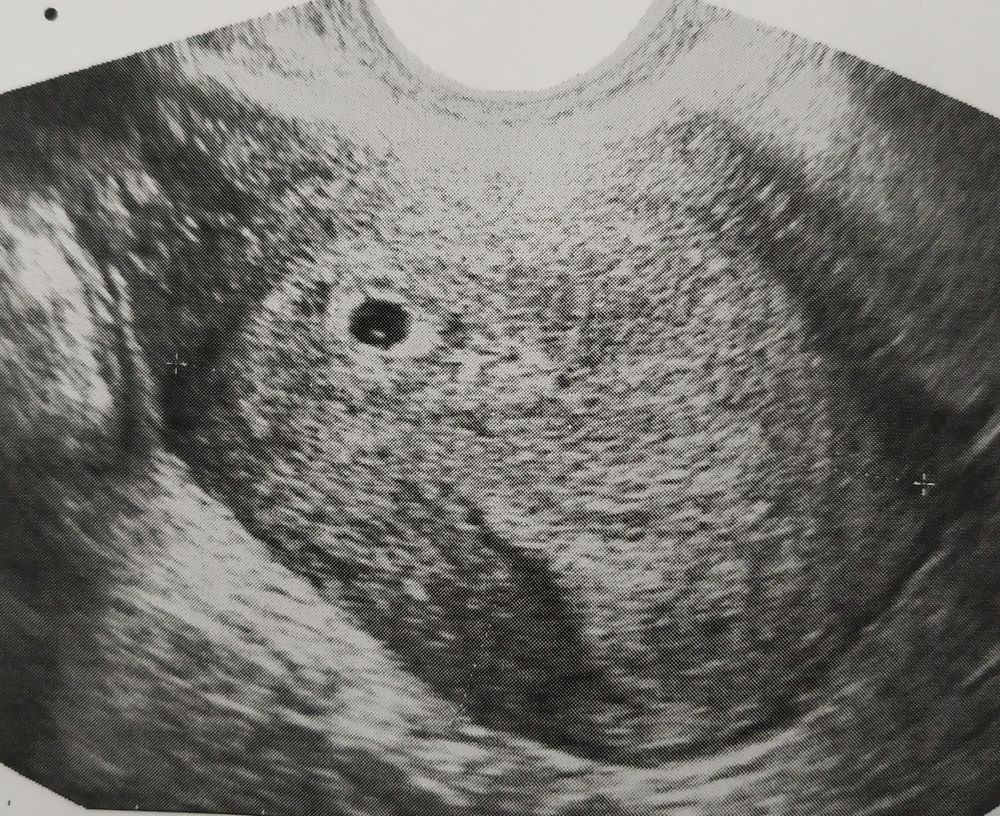

УЗИ. Беременность или нет?

Была сегодня на УЗИ. Срок 6 акушерских недель. Беременность не подтвердили. В матке образование 4 мм. Плодное яйцо под вопросом. Врач сказала, что пока не понятно, может через неделю это превратится в беременность.

Но я что-то сомневаюсь, по идее на этом сроке уже сердечко биться должно. 4 мм это мало. Может у кого-то было такое же УЗИ в 6 недель?

Ну это ПЯ 100% даже что-то внутри есть. Только да, для этого сроко слишком маленькое.

Ну видимо беременность, раз у вас результат в кружочке))